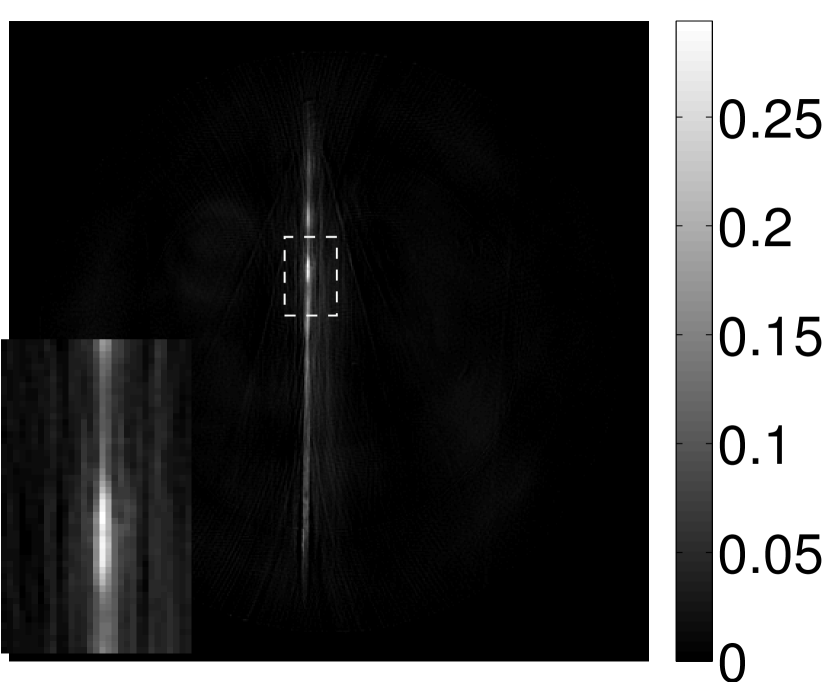

Figure 11 displays images of the needle phantom reconstructed by use of the simple backprojection method [BM2003]. Figures 12 and 13 display the images reconstructed by use of the conventional iterative method and VP algorithm, respectively.

Figures 12 and 13 show that the width of the needle in the reconstructed image increases as the regularization parameter increases for both the conventional iterative method and the VP algorithm. The images reconstructed by use of the VP algorithm appear to have a reduced noise level compared to the images reconstructed by the backprojection and conventional iterative methods, regardless of the choice of the regularization parameter values. The profile plots corresponding to these three methods are shown in Figure 14. Since the image of the coefficient vector and the EIR are recoverable only up to a multiplicative constant, every profile was normalized for comparison. These plots demonstrate that the image reconstructed by use of the VP algorithm possessed a more uniform background than those obtained by the backprojection and the conventional iterative methods.